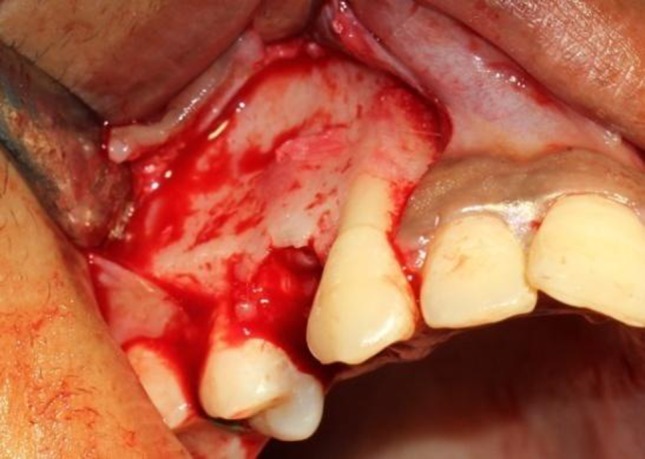

For PLD side crevicular incisions were made extending from mesial interdental papilla of 2nd premolar to the distal interdental papilla of the lateral incisor with a vertical releasing incision on either side into the veatibule placed to raise mucoperiosteal flap 6 mm above the canine and first premolar to allow for the planned undermining of the interdental septa (Fig. 2). After the first premolar extraction, the interseptal bone distal to the canine was undermined with a straight fissure bur, grooving vertically inside the extraction socket along the buccal and palatal sides, and extending obliquely toward the base of the interseptal bone to weaken its resistance (Figs. 3, 4). The depth of the undermining grooves was dependent on the thickness of the interseptal bone, as revealed on the periapical films.

Fig. 2.

Raising flap in the PLD side